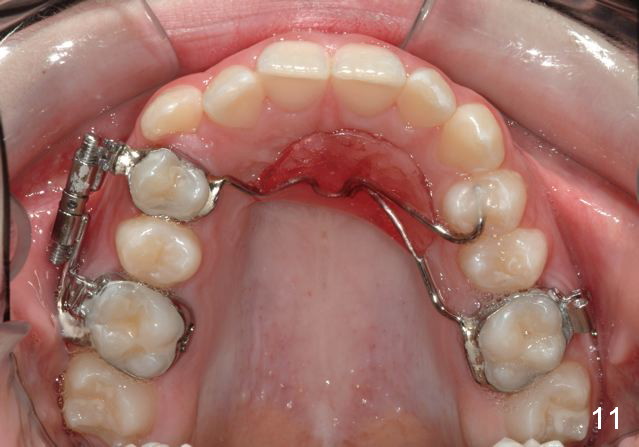

Rapid Molar Distalizer is placed (Fig.11). It is turned twice a week. UR6,7 are bodily distalized to Class I with gaining of the arch length 4 months 11 days later (Fig.12,14) without adverse effect on U midline (Fig.13). Final result?